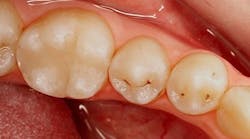

Identification of occlusal pit caries is aided by visual cues of white opacities at the entrance of grooves and enamel roughening within the groove. Identifying these lesions may be aided by tools that employ light-induced fluorescence. Red laser light-based (655 nm wavelength) devices (DIAGNOdent Pen, KaVo) provide a number to indicate the amount of fluorescence reflected from bacterial byproducts, whereas blue light-based (400-450 nm wavelength) devices (DIAGNOcam, KaVo; CamX Spectra, Air Techniques) produce a map on the tooth of luminous intensity in areas where there is bacterial activity. Blue light-based devices are reported to be more accurate than red laser light-based devices.6 Radiographic evidence of occlusal caries is not observed until later stages of demineralization.